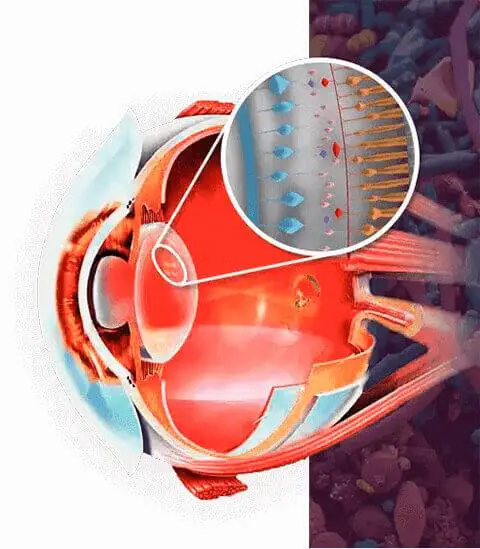

Los ojos son una de las partes más importantes del cuerpo. Además de ser el órgano de la visión, también actúan como guardianes, percibiendo todo aquello que nos genera incomodidad. Cuidar la retina es una de las claves para mantener una buena salud ocular. La retina desempeña un papel vital, ya que se encarga de procesar la información visual que luego se transmite al cerebro. Sin embargo, existen varios factores que pueden deteriorar la visión:

- El daño en el sistema muscular que enfoca los ojos hace que la imagen que pasa por el cristalino se proyecte incorrectamente sobre la retina.

- Mejora la agudeza visual y fortalece la retina